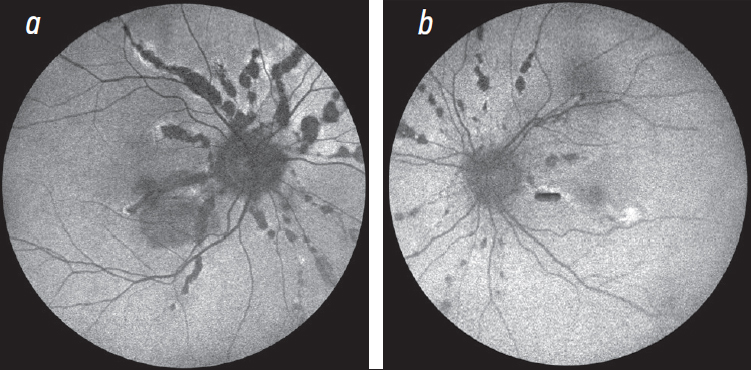

- ангиоидные полосы сетчатки — участки повреждения мембраны Бруха, которые представляют собой неровные, прерывистые линии, идущие чаще радиально от диска зрительного нерва и распространяющиеся к периферии. Полосы имеют сходство с хориоидальным сосудистым рисунком, а их цвет может варьировать от серого и тёмно-красного до бледно-жёлтого, могут быть пигментированы, длительно существующие ангиоидные полосы белеют вследствие потери хориокапилляров (рис. 2, а). Ангиоидные полосы — не патогномоничное проявление эластической псевдоксаномы, так как могут присутствовать и при таких заболеваниях, как серповидно-клеточная болезнь, талассемия и реже синдром Элерса – Данлоса [19–22];

Рис. 2. Фотография глазного дна правого и левого глаза. В заднем полюсе правого глаза тёмно-красные сосудоподобные линии (ангиоидные полосы) с жёлтыми зонами атрофии, радиально расходящиеся от диска зрительного нерва к периферии: a — твёрдые экссудаты в макулярной зоне, субретинальное кровоизлияние и фиброз; b —тёмно-красные ангиоидные полосы в заднем полюсе левого глаза. В макулярной зоне ангиоидные полосы проходят парафовеолярно

Fig. 2. The fundus photo of the right and left eyes. In the posterior pole of the right eye, there are dark red vascular-like lines (angioid streaks) with yellow areas of atrophy radially diverging from the optic disc to the periphery: a — hard exudates in the macular area, subretinal hemorrhage and fibrosis; b — dark red angioid streaks in the posterior pole of the left eye. In the macular area, angioid streaks are located in the parafoveal zone

При офтальмоскопии: на глазном дне обнаружены ангиоидные полосы. На правом глазу также выявлены точечные, жёлтые друзоподобные скопления в височной половине макулярной зоны (изменения глазного дна по типу апельсиновой корки). В макулярной зоне парафовеолярно по ходу одной из ангиоидных полос визулизировался участок субретинального фиброза, мелкие твёрдые экссудаты и субретинальная геморрагия, затрагивавшая фовеолярную зону (рис. 2, а).